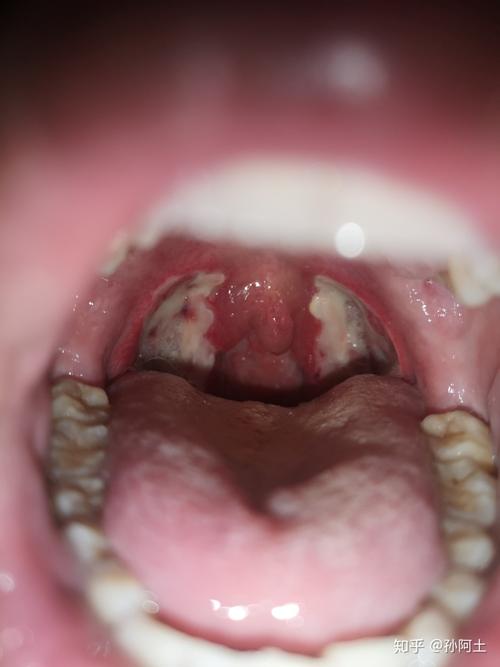

扁桃体术后疤痕图片

扁桃体术后疤痕图片,扁桃体术后正常图片

扁桃体术后正常图片

扁桃体手术后痊愈图片

扁桃体术后图片

扁桃体手术伤口恢复图

扁桃体术后恢复过程图

扁桃体术后恢复照片